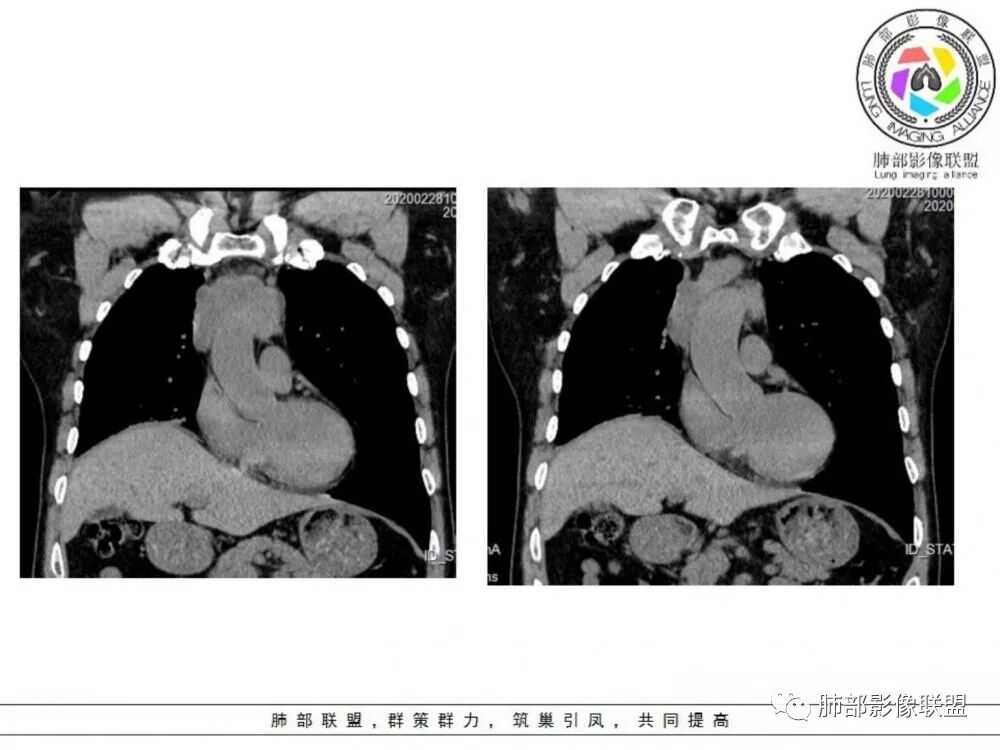

男性患者,65岁,前胸后背疼痛一个月。影像学前上纵隔分叶状的软组织肿块,肿块形态怪异,偏软,位于大血管间隙前,并有向血管后间隙发展的趋势,平扫CT值为40左右,增强扫描中心部未见强化,周围轻度的强化,约为50左右。前上纵隔的疾病谱包抬胸廓内甲状腺肿、胸腺瘤/癌、畸胎瘤、淋巴瘤。少见的心包囊肿或支气管囊肿。根据肿块的形态及强化特点,首先还是排除了胸内甲状腺肿及胸腺来源的肿物,这类的肿物强化比较明显。畸胎瘤成分比较复杂,具有软组织钙化或者脂肪类的组织,这个肿物虽然在平扫的时候好像有斑点状的钙化灶,但是总体成分还是比较单一,所以还是排除畸胎瘤的诊断。所以这样的情况是考虑:淋巴类的肿瘤,注意排除心包的囊肿或支气管来源的囊肿。

临床,老年男性,病史一月。1 定位,骑跨大血管,大部分位于胸腺区域内,周边部分胸腺脂肪有混浑浊,起源于胸腺区的组织应该没有问题。2 定性 。恶性征像,分叶,大血管侵润,pet高代谢,左侧庄层胸膜增厚(类似脑膜瘤的脑膜尾征,良性表现?)。良性征像,病灶均匀,无明确坏死?综合恶性征像多些,考虑恶性可能大。病灶分两部分,部分层面似有明确分割,两个性质的病灶长一块,还是,一个病灶两种不同成分?一个病灶伴均匀坏死?CT值41hu,坏死好像高了点,一个病灶,相同成分,只是血管分布不同,增强是持续流入型强化。纤维类?编不下去了,岔路太多,祭出法宝按概率蒙吧:侵袭性胸腺瘤>神经纤维瘤>乏血供CD

老年男性,定位前纵隔,似乎有点塑形生长,肿块与大血管分界欠清,上腔静脉局部包绕受压,侵犯?增强扫描低强化。考虑恶性,胸腺癌可能。鉴别淋巴瘤。

老年男性,前纵隔不规则软组织肿块影,密度欠均匀,与大血管分界欠清,上腔静脉局部包绕受侵,增强扫描不均匀轻度强化,PET-CT高代谢。考虑恶性肿瘤性病变,胸腺癌可能。鉴别淋巴瘤。

男性患者,65岁,前胸后背疼痛一个月。胸部影像:前上纵隔分叶状的软组织肿块,形态不规则,包绕大血管生长趋势,与周围分界不清,密度较均匀,呈多结节融合,肿块周围可见肿大淋巴结,内乳动脉旁淋巴结大,上腔受累,肿物内可见低密度区,增强扫描周围轻度强化。考虑:恶性病变,淋巴瘤?胸腺神经内分泌肿瘤?鉴别胸腺瘤

中老年男性,前纵隔占位,基本居中,向两侧生长;边缘膨隆分叶,部分边界不清,增强不均匀轻中度强化,坏死区边界不清;周围多发增大淋巴结,考虑恶性。主要在胸腺癌、胸腺瘤、淋巴瘤之间鉴别。病灶偏软,有钻缝样生长,这些征象偏向于淋巴瘤。但此例老年患者,病灶内有点状钙化,缺乏结节堆砌感,倾向胸腺癌诊断。